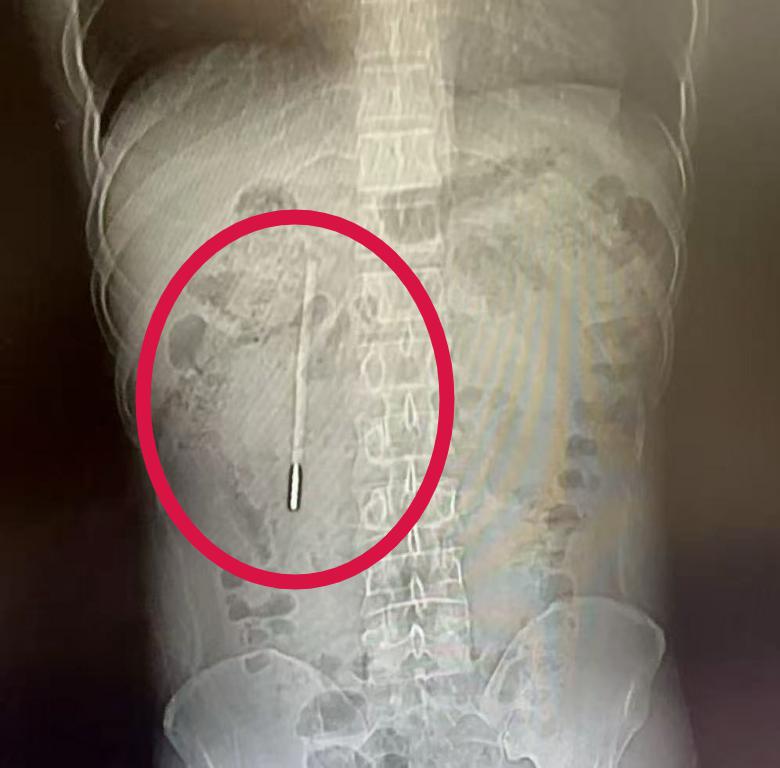

浙江一男子12岁误服水银温度计,到32岁时才取出

浙江温州 32 岁的王先生

因腹部不适就医,

结果在 CT 检查中发现

其十二指肠内

竟藏有一根清晰的异物,

经追溯病史

这竟然是他 20 年前、年仅 12 岁时

不慎误吞的

一根水银体温计!

这根体温计在患者体内 " 潜伏 " 了整整二十年,其前端当时已抵近肠壁,存在引发穿孔、大出血等严重并发症的潜在风险。由于事发时王先生年仅 12 岁,因害怕没有告知家长,而家人也没有察觉到异常,此事便一直被搁置下来,直到这次腹痛就医才被发现。

体温计滞留时间极长、位置较深,且毗邻关键的胆管和胰管,操作空间十分狭窄,稍有不慎就可能导致肠壁损伤。面对这一高风险病例,温州医科大学附属第一医院龙港院区的内镜中心医护团队在相应器械辅助下精准定位,用圈套器套住体温计一端,通过缓慢轻柔的提拉,成功将整根体温计从王先生的十二指肠处取出。

令人称奇的是

这根 " 跨越 " 了二十年的体温计

除刻度已消失外

外观基本完好无损